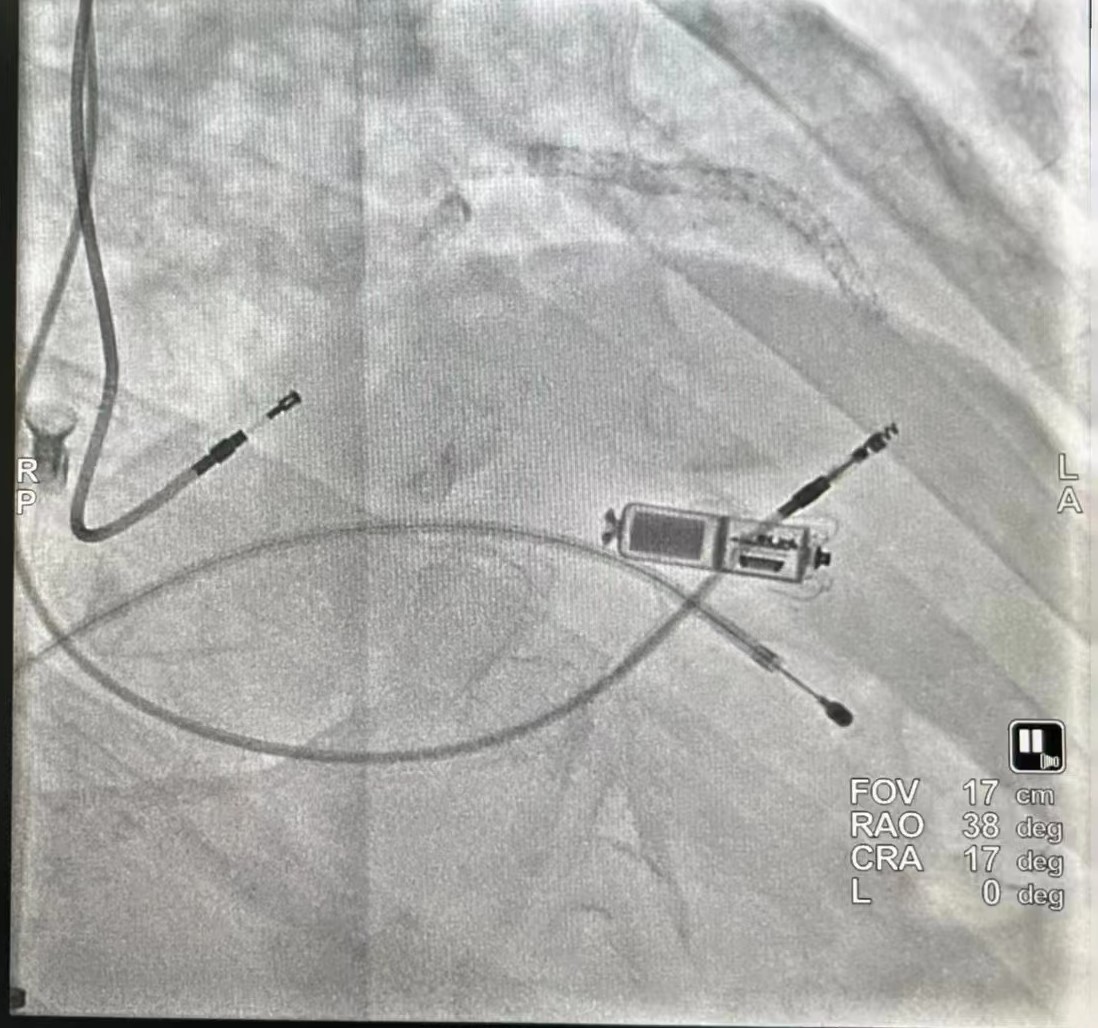

在临时起搏器保护下,穿刺右侧股静脉送Micra递送系统经右心房跨三尖瓣送抵中位间隔处,透视见电极贴壁良好,原位释放起搏器,行牵拉试验示起搏器固定良好,剪断栓绳后撤出输送鞘管,缝合伤口予以加压包扎。术程顺利,起搏器工作良好。术中更是留下了永久电极、临时电极、无导线起搏器、冠脉支架共现的场景!